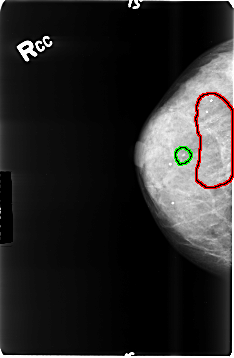

FILE: B_3496_1.RIGHT_CC.OVERLAY

TOTAL_ABNORMALITIES 2

ABNORMALITY 1

LESION_TYPE CALCIFICATION TYPE PUNCTATE-AMORPHOUS DISTRIBUTION REGIONAL

ASSESSMENT 4

SUBTLETY 4

PATHOLOGY BENIGN

TOTAL_OUTLINES 1

BOUNDARY

ABNORMALITY 2

LESION_TYPE CALCIFICATION TYPE PUNCTATE-AMORPHOUS DISTRIBUTION CLUSTERED